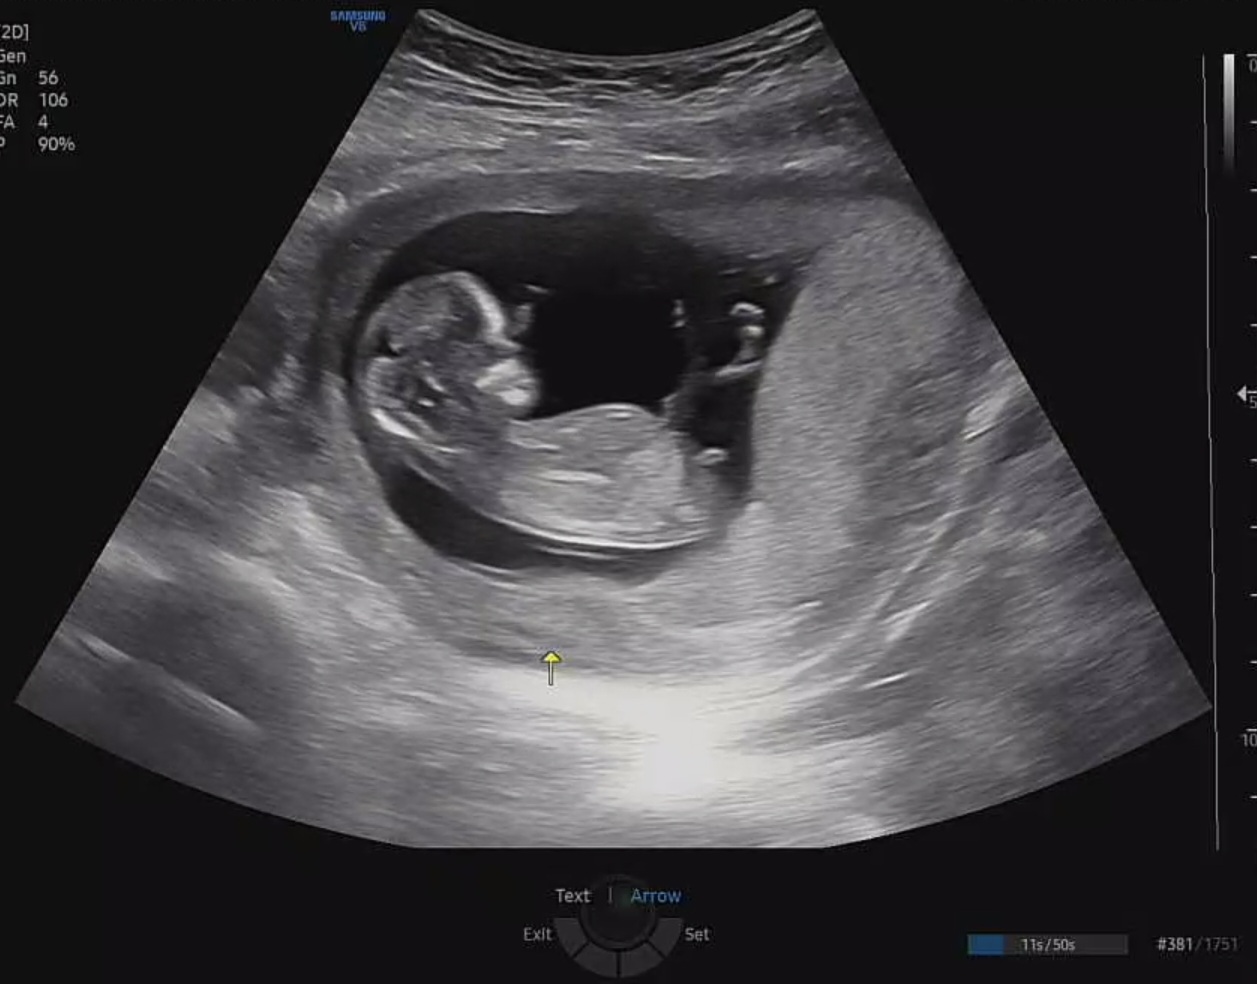

12주 각도법 딸일까요?아들일까요?

오늘 12주차 초음파 보고왔어요 딸일까요?아들일까요? 너무 궁금해요 많이들 투표 부탁드려요🙏🏻